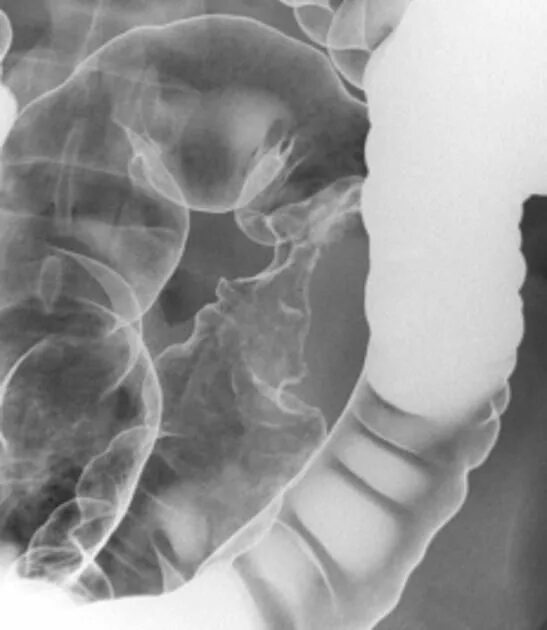

Долихоколон симптомы у взрослых